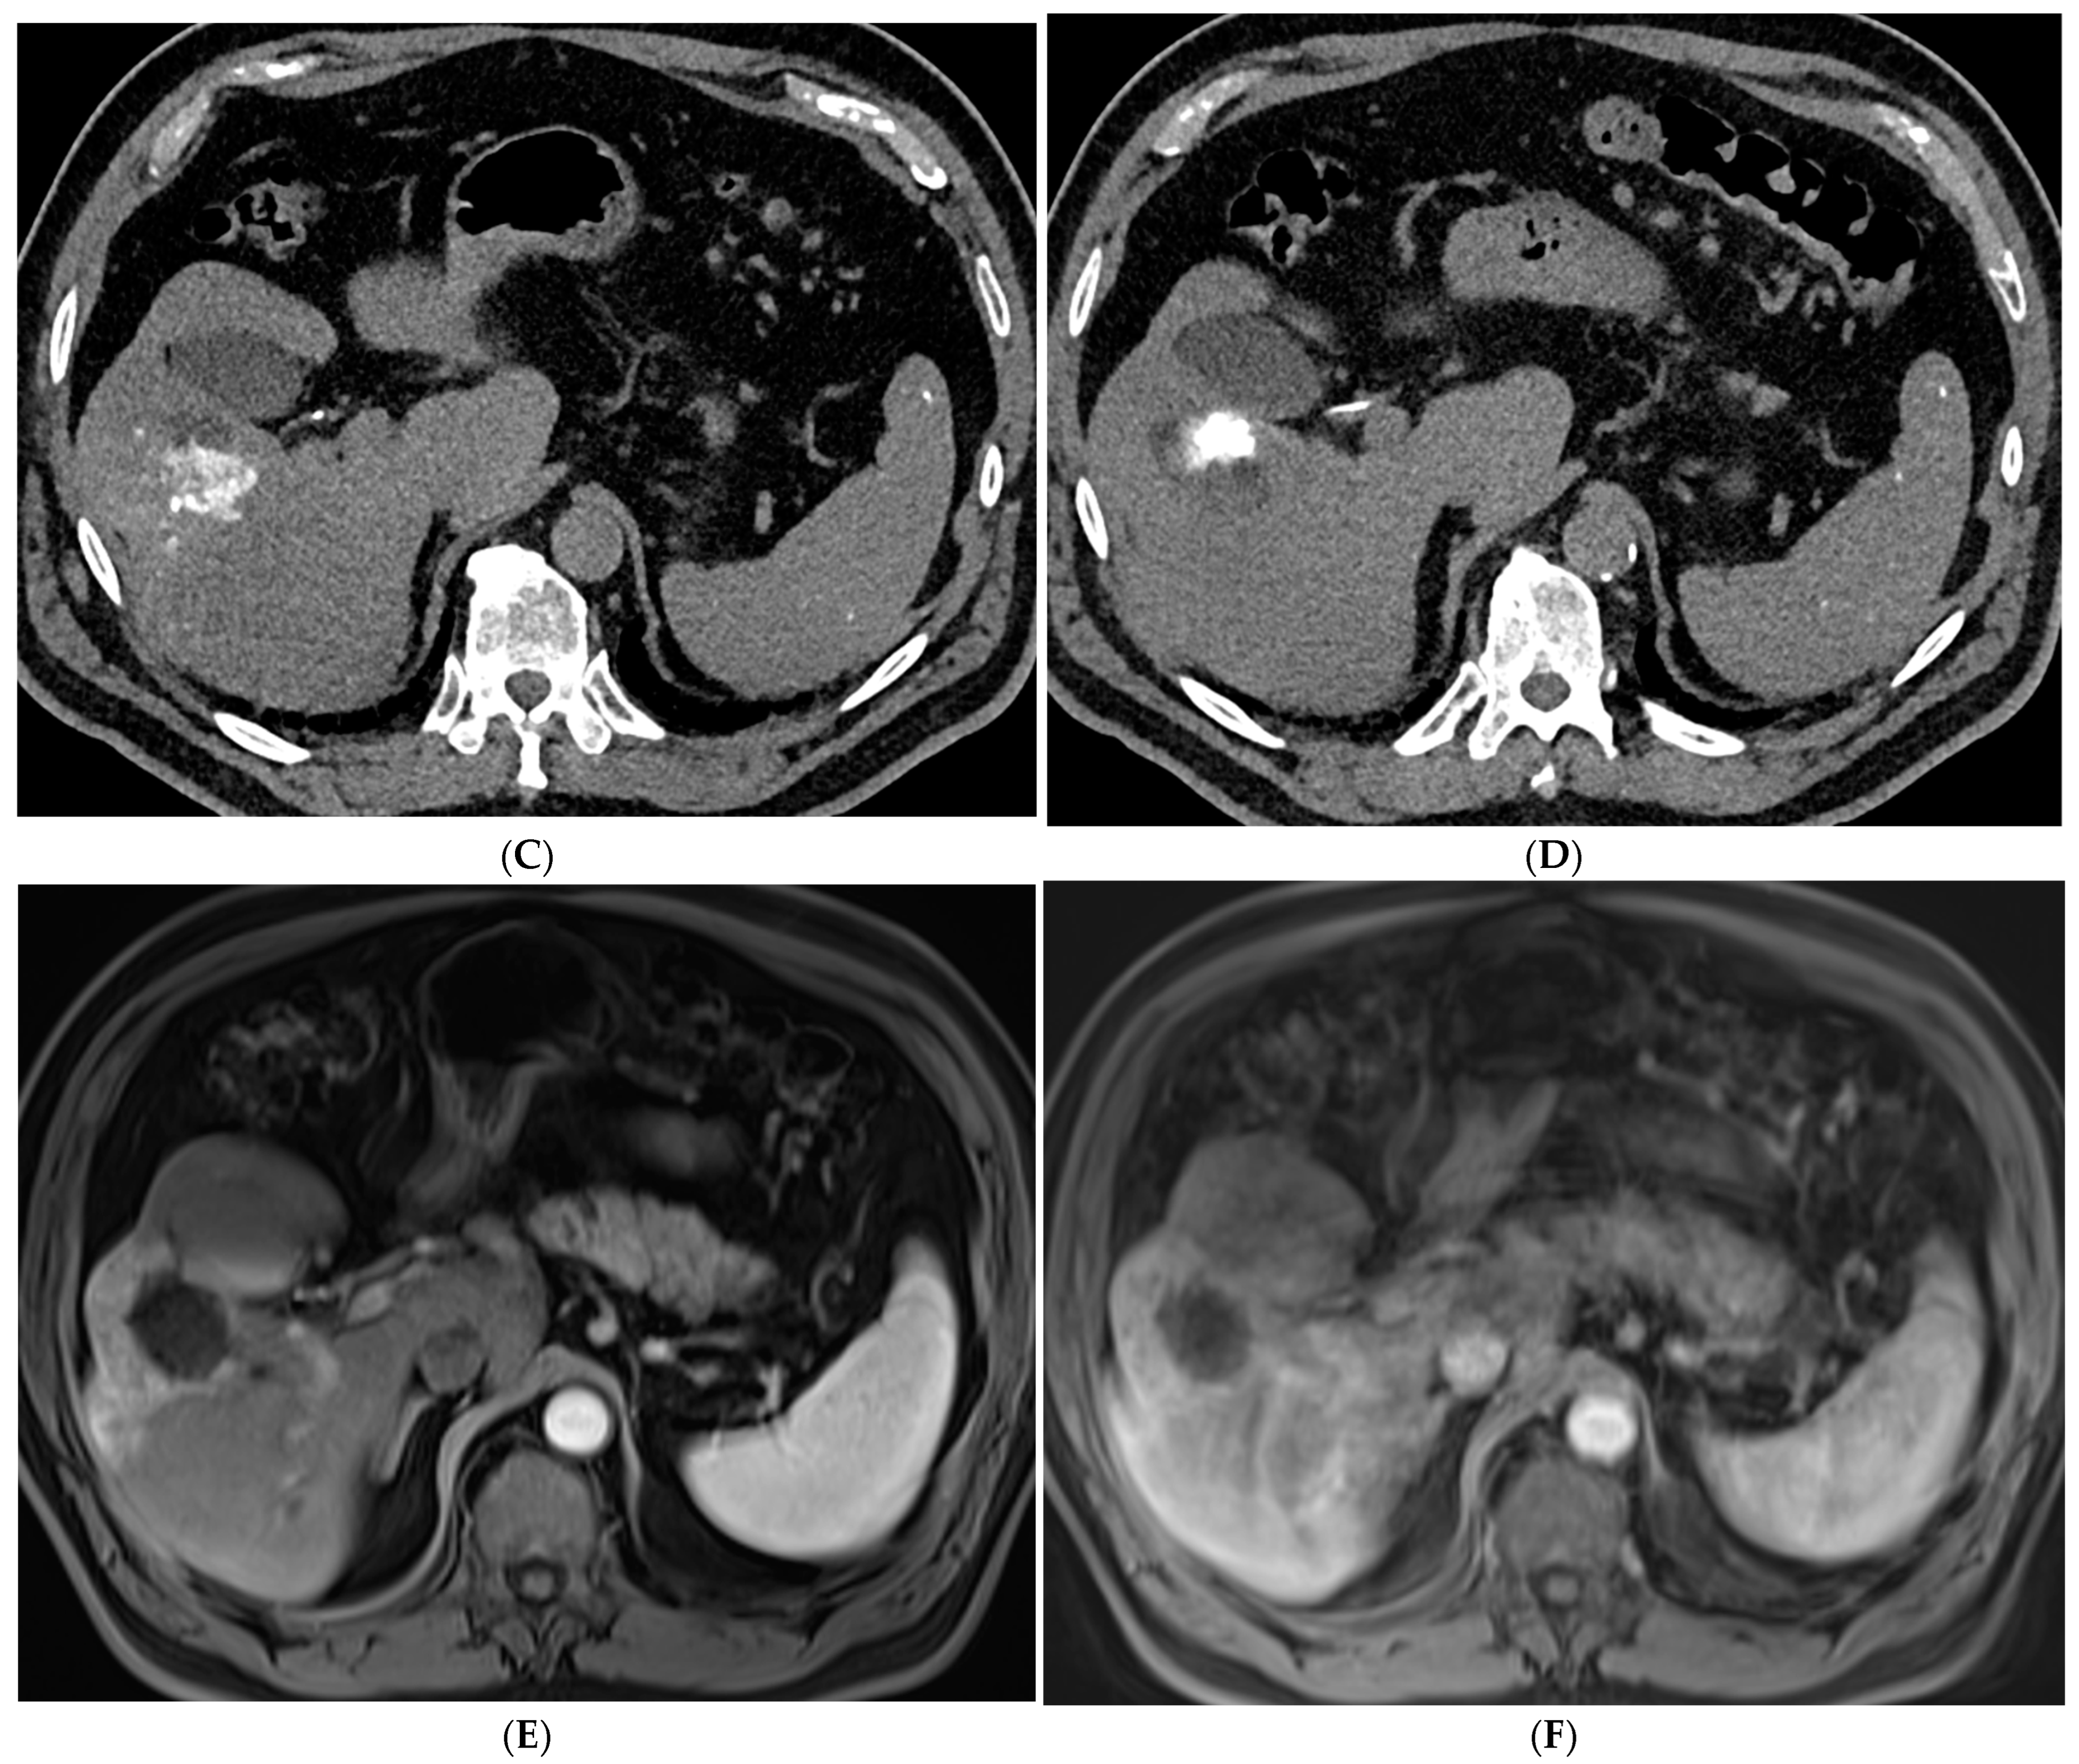

Figure 4. 72-year-old man with HCV cirrhosis and HCC treated with combined cTACE and cryoablation as a bridge to transplant. (A) Arterial phase MRI demonstrates a 2.2 cm segment 4a hypervascular lesion. (B) Digital subtraction angiography images during cTACE procedure demonstrate that the tumor was supplied by both the segment 4a branch vessel (image shown) and segment 2 artery (not shown). cTACE was performed using doxorubicin 50 mg, cisplatin 100 mg, and mitomycin 10 mg followed by PVA 150–250 micron particles. (C) A non-contrast CT scan performed on post-operative day 1 demonstrates a heterogeneous uptake of ethiodized oil within the tumor. Cryoablation was then performed using two probes. Coronal and axial CT images from the procedure demonstrate the probes adjacent to the ethiodized oil staining (D) and the ice ball (E). (F) A follow up contrast enhanced MRI in the arterial phase demonstrates no residual viable tumor.

The combination of locoregional therapies is also an area of interest. In a meta-analysis, the combination of TACE and RFA compared to surgical resection showed no difference in overall survival but reduced complications in the combination therapy group [65]. The ethiodized oil retention within HCC following cTACE can also be used as a marker to guide percutaneous ablation (Figure 4). Stereotactic body radiotherapy (SBRT) is currently being studied in combination with TACE with promising results. In a propensity-scored matched analysis by Wong et al., patients who received the combination of SBRT + TACE had significantly higher one- and three-year overall survival and improved radiological disease control [66]. There is also interest in using SBRT in cases of local relapse following TACE. A phase III trial was closed early due to slow accrual, but results showed superior local control of SBRT versus repeat TAE/TACE [67]. SBRT remains a promising non-invasive treatment for unresectable HCC. Further research is needed to define its role within the HCC treatment paradigm.